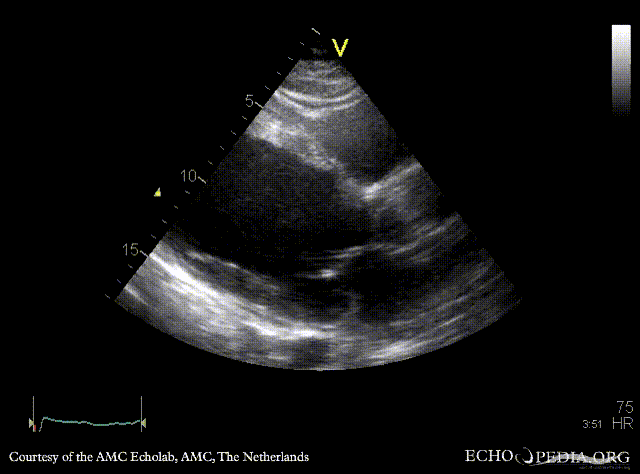

E00219.gif E00220.gif

PLAX: cardiac aneurysm, spontaneous echo contrast A4CH: cardiac aneurysm, spontaneous echo contrast